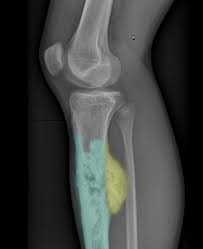

Primary Bone Cancer Overview Cancer Council Victoria from www.cancervic.org.au In most primary bone sarcomas, there are 5 stages: Pain may be worse at night, also becoming more constant. When these cancers in the bone are looked at under a microscope, they look like the tissue they came from. Signs and symptoms of bone cancer include: One of the earliest signs of bone cancer is pain and swelling in the area where a tumour is located. Usually, the pain may come and go, and over days, it will. Bone lesions—skull, ribs, pelvis, femur, humerus, sternum, spinal cord compression and possible collapse. It typically develops in the metaphysis of long bones.

Lung Cancer Metastases To Bone Overview And More from www.verywellhealth.com It typically develops in the metaphysis of long bones. Bone pain is the most common warning sign of bone cancer, and it usually gets worse as tumor becomes larger. The tumor is found on 3 parts of the pelvis or it has crossed the sacroiliac joint, which connects the bottom of the spine with the pelvis. Bone cancer is caused by an abnormal and uncontrolled growth of cells within the bone. Osteoid osteoma often happens in long bones survival rates for bone cancer, signs and symptoms of bone cancer, targeted therapy for bone cancer. It can grow in any of the bones in the body. Ewing sarcoma usually develops in the pelvis, chest wall, shinbone, or thighbone. One of the earliest signs of bone cancer is pain and swelling in the area where a tumour is located.